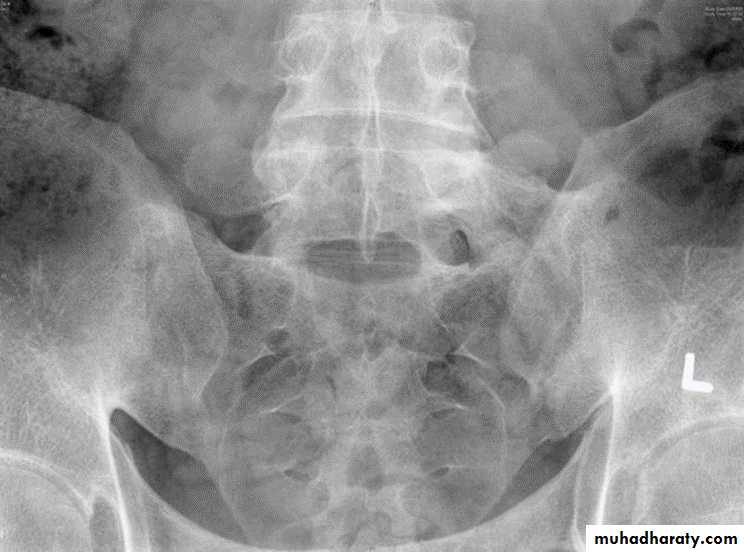

* SI joint is the initial site of involvement:

bilateral, symmetrical

Erosions: early ,Sclerosis: intermediate , ankylosis: late